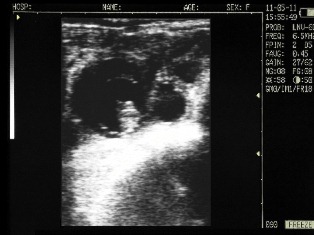

Ultrasound images of cows reproductive system, generated by a scanner Sonovet with rectal linear transducer.

Filled bladder cow